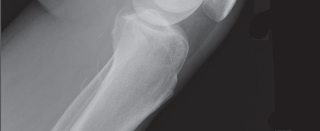

High-quality, standardized, weight-bearing radiographs are the cornerstone of preoperative planning. A standard knee series must include a weight-bearing anteroposterior (AP) view, a weight-bearing lateral view in extension, and a skyline (Merchant) view of the patella. The AP view reveals joint space narrowing, subchondral sclerosis, osteophyte formation, and the presence of subchondral cysts. The lateral view is essential for assessing patellar height (Insall-Salvati ratio) and the posterior slope of the tibia.

Crucially, we must obtain a 45-degree posteroanterior (PA) weight-bearing view (the Rosenberg view). Because cartilage wear in early-to-moderate OA predominantly affects the posterior aspect of the femoral condyles, the standard extension AP view may falsely appear normal. The flexed Rosenberg view unloads the patella and brings the worn posterior condyles into contact with the tibia, revealing hidden joint space narrowing. Furthermore, a full-length, hip-to-ankle standing radiograph is highly recommended, particularly in patients with severe deformities or a history of prior femoral/tibial fractures, to accurately determine the mechanical axis and identify any extra-articular deformities that might complicate intramedullary instrumentation.